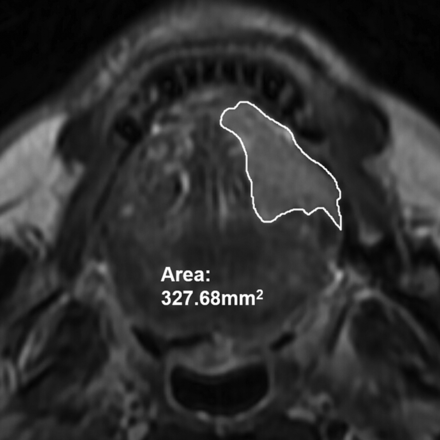

Tumor thickness and tumor volume were measured by using axial T2WI according to methods taken from previous studies.3,5⇓–7 Tumor thickness was defined as the distance from the tumor surface to the deepest point of invasion. Meanwhile, after the lesion-involving area in each section was delineated by using an operator-defined ROI, the tumor volume was obtained from the sum of the areas multiplied by the section interval. The methods used for the MR imaging–based measurement of tumor thickness and tumor volume are shown in Figs 2 and 3, respectively. Imaging analysis was performed independently by 2 dedicated head and neck radiologists blinded to the pathologic results. The mean values of their measurements were calculated for further statistical analysis.

The lesion in each section was delineated by using an operator-defined ROI, and the volume was obtained by multiplying the entire area by the section interval.